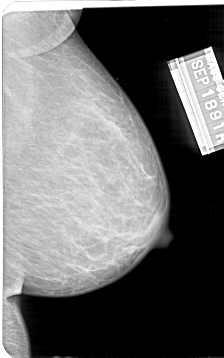

A_1568_1.LEFT_MLO

LEFT_MLO LINES 5086 PIXELS_PER_LINE 3346 BITS_PER_PIXEL 12 RESOLUTION 43.5 OVERLAY